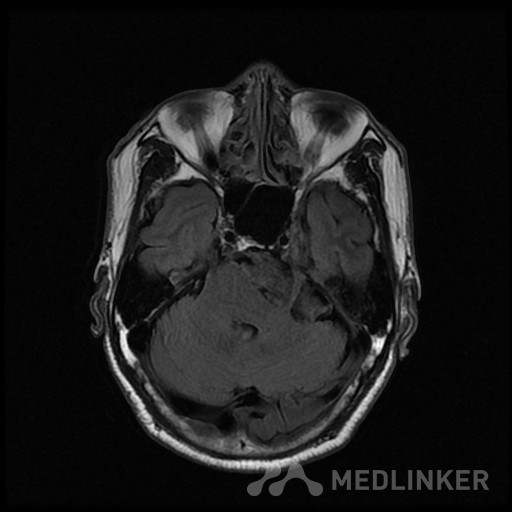

桥小脑区长T1长T2囊状病灶(如图),考虑表皮样囊肿还是蛛网膜囊

如图所示,左侧桥小脑区的囊状长T1长T2异常信号,增强扫描未见强化。考虑表皮样囊肿还是蛛网膜囊肿?